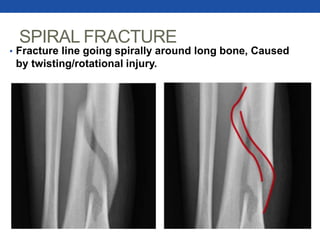

SPIRAL FRACTURE

• Fracture line going spirally around long bone, Caused

by twisting/rotational injury.